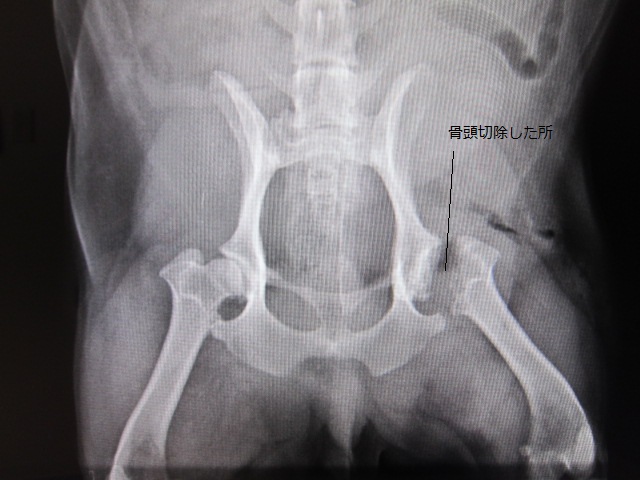

術前

術前のレントゲンです。

右の股関節と比較すると一目瞭然です。